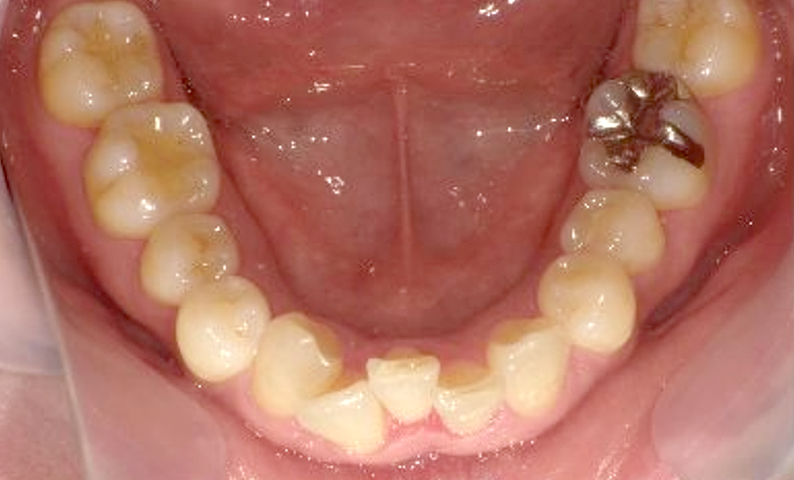

症例_002 下顎だけの部分矯正

治療期間:6ヶ月金額:21万円+税女性前歯のデコボコ下の前歯だけ

| Before | After |